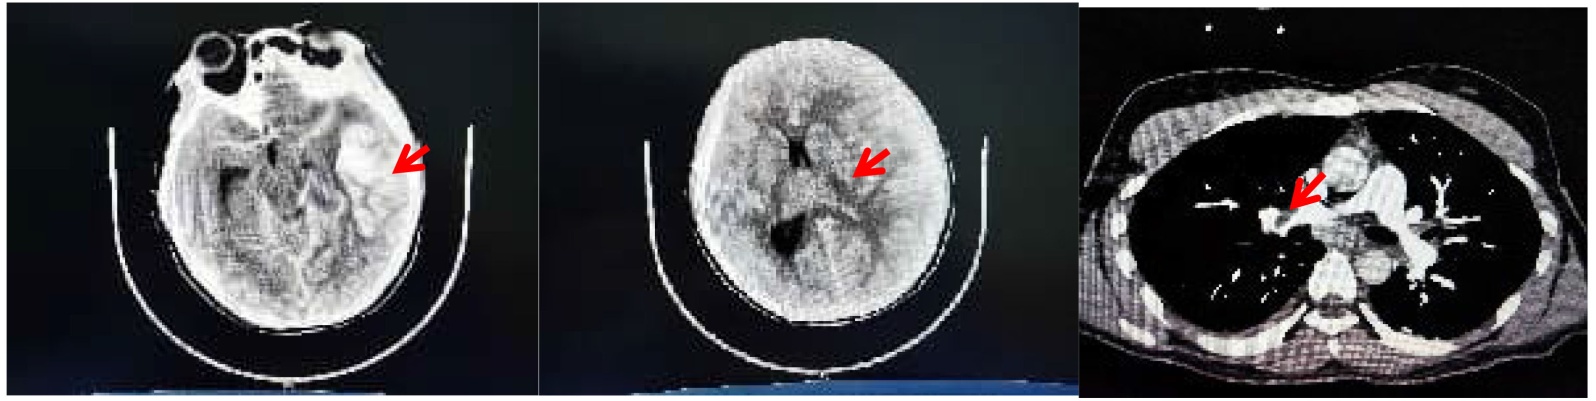

血常规:白细胞10.57 × 109/L,血小板9 × 109/L,中性粒细胞百分比77%,血红蛋白31 g/L;血气:pH 7.437,二氧化碳分压34.7 mmHg,氧分压96.5 mmHg,乳酸0.8 mmol/L,碳酸氢根23.4 mmol/L;血生化:肌酐40 mmol/L,谷丙转氨酶17 U/L,心肌肌钙蛋白 < 0.003 ng/L,B型钠尿肽前体680 pg/mL;凝血:凝血酶原时间15.5 s,国际标准化比值1.33,纤维蛋白原3.44 g/L,活化部分凝血酶原时间37.9 s,D-二聚体30.7 mg/L;C反应蛋白76.46 mg/L;抗心磷脂抗体IgM为4.61 mpl/mL (参考范围:<20.0)、抗心磷脂抗体IgG为4.37 mpl/mL (参考范围:<20.0)、抗β2-糖蛋白1 IgG抗体为8.08 U/mL (参考范围:<20.0);抗β2-糖蛋白1 IgM抗体为4.47 U/mL (参考范围:<20.0);狼疮抗凝物标准比值为1.12 (参考范围:0.80~1.20);余抗核抗体谱、抗ENA抗体、补体、抗凝血酶III、蛋白S、蛋白C、ADAMTsl3活性均正常。头部平扫:(1) 左侧颞叶多处血肿形成,周围脑组织水肿;(2) 左侧额颞顶部硬膜下血肿;(3) 蛛网膜下腔出血;(4) 左侧脑室后角内少许积血可疑;(5) 大脑镰下疝。肺动脉成像 + 腹部增强CT提示:右肺动脉散在少量栓塞,右上肺动脉主干为甚,双肺散在炎症合并间质性肺水肿;静脉超声:右侧锁骨下、肘静脉、贵要静脉、肱静脉(双支)、腋静脉血栓形成;双侧股总、股浅、腘、腓、胫后及小腿肌间静脉血栓形成,双侧头静脉、双侧颈内静脉血栓形成。如图1所示(我院超声没有图像报告,只有文字报告)。

Figure 1. Cerebral hemorrhage, cerebral herniation, pulmonary embolism

1. 脑出血、脑疝、肺动脉栓塞